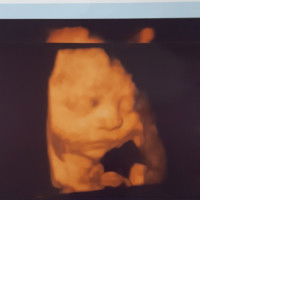

Pwd ba ung iron na sangobion iron plus sa ating mga buntis? Ng pa bili lang po kasi ako pero instead na sangobion prenatal fa . Sangobion iron plus po nabili ?. Pls po sana mai maka sagot